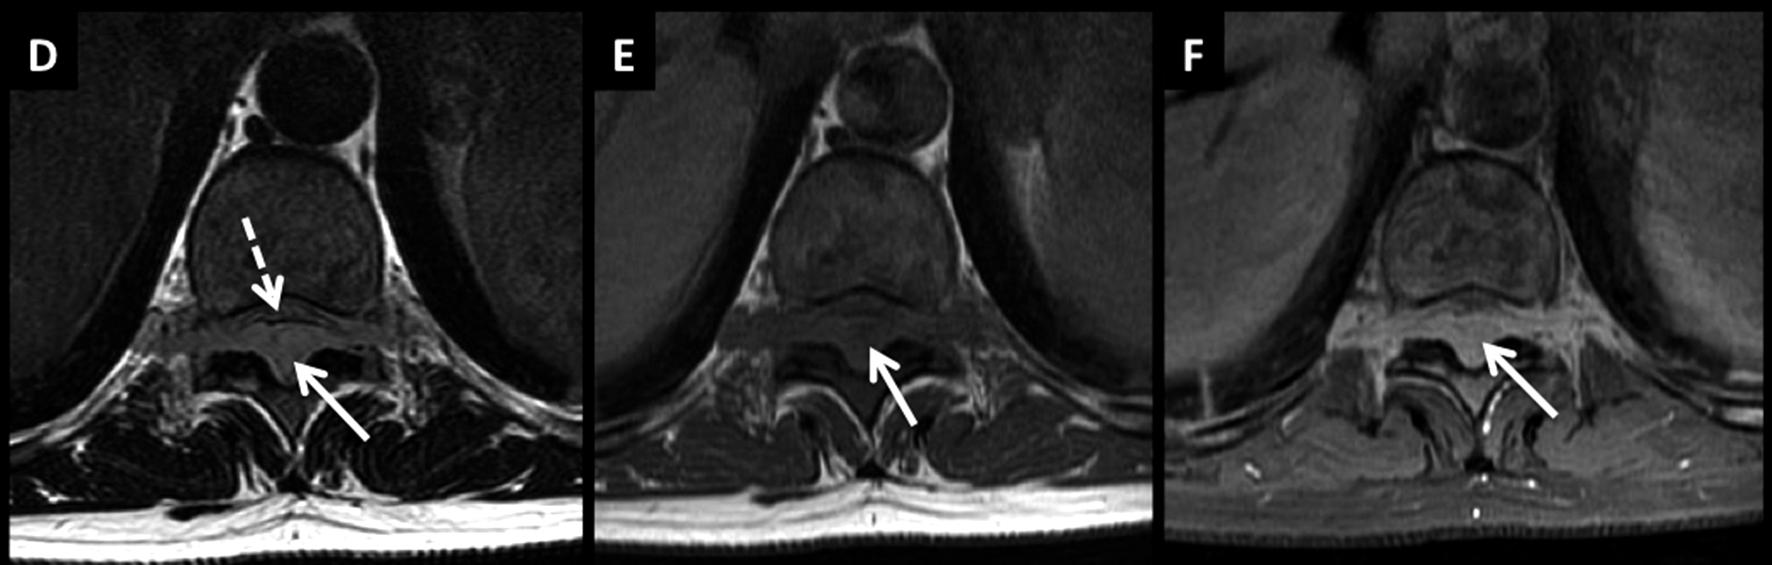

Figura 7

LNH, infiltración de cola de caballo, compromiso leptomeníngeo secundario.

Paciente joven con LNH y síndrome radicular asociado. En el estudio de estadificación se encuentra un patrón de infiltración de las raíces de la cola de caballo y se confirma el diagnóstico por estudio citológico del líquido céfalo raquídeo.

Este tipo de patrón se caracteriza por raíces nerviosas engrosadas que luego de administrar medio de contraste (D a F) presentan intenso realce.

El proceso infiltrativo rodea al cono medular (flecha discontínua) y puede contribuir a la clínica del paciente.